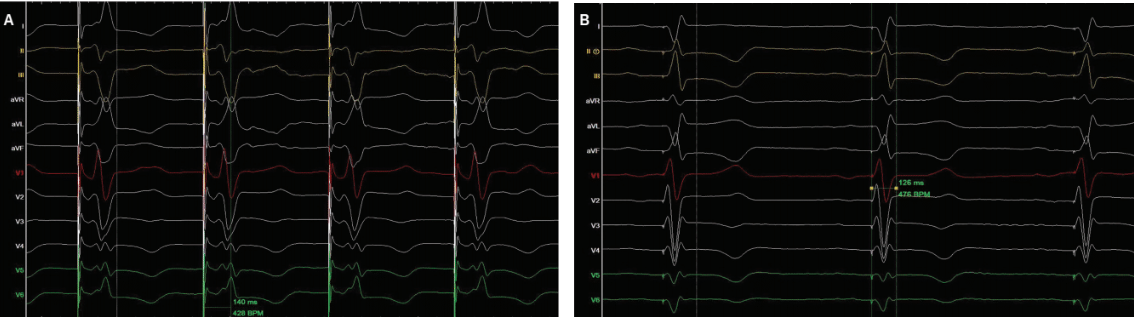

A 67-year-old man with a history of ischemic cardiomyopathy, s/p coronary artery bypass grafting, and dual-chamber implantable cardioverter-defibrillator implantation for primary prevention was referred to our center for CRT upgrade due to complete heart block and high burden of ventricular pacing. Device interrogation revealed stable lead parameters and 100% pacemaker dependency. Clinical examination was unremarkable. Functional capacity (NYHA) was II-III. Baseline 12-lead electrocardiogram (ECG) showed paced rhythm (ApVp) at a rate of 60 beats per minute (bpm) and paced QRS duration of 177 ms (Figure 1A). Transthoracic echocardiography revealed severely depressed left ventricular (LV) function (LV ejection fraction of 25%) and dilated LV (LV end-diastolic volume of 68 mm, LV end-systolic volume of 49 mm). The patient was scheduled for CRT or CSP upgrade.

After obtaining both verbal and written consent, the patient was taken to the laboratory. The device therapy was turned off and the mode was changed to DOO. A venogram was performed and showed vein patency. Two axillary venous access were obtained. The Selectra 65/39 delivery sheath (Biotronik) was used to engage the septum. A Solia S 60-cm lead (Biotronik) was prepared for septal penetration. A good septal spot was found and the lead penetrated towards the LV septum (Video 1). Although unipolar pacing showed a right bundle branch block pattern and stable lead parameter, the V5-R Wave Peak Time (RWPT) was too long (140 ms) (Figure 2A). Therefore, we opted to implant an LV lead as well. The coronary sinus (CS) was engaged and good lateral branch was observed. A quadripolar LV lead was placed into the lateral branch (Video 2). Lead parameters were stable with no evidence of phrenic nerve stimulation. Both the Selectra sheath and CS sheaths slitted with no evidence of lead dislodgements. Leads attached to the device (Intica Neo 5 HF-T, Biotronik). The device was programmed as DDD @50 bpm, LV>RV offset of 20 ms, and atrioventricular delay (AVD) of 120 ms (Figure 2B). The final paced QRS duration was 126 ms (Figure 1B). The patient was discharged same day and no acute complication was noted.

In patients not responding to standard CSP, His-optimized CRT (HOT-CRT) and left bundle-optimized (LOT-CRT), delivered as CSP in combination with an LV epicardial lead, have been proposed as alternative delivery methods to resynchronize the ventricles.6,7 In these patients, the addition of an LV lead (LOT-CRT) might result in better electrical resynchronization and narrower QRS duration as well as QRS area.8 In our case, adding the LV lead resulted in narrower QRS duration compared to LBBAP alone (126 ms vs 180 ms). A recent study described the effect of different conduction system disturbances on various CSP modalities with the use of computational modeling and found that patients with diffuse LV conduction system disease showed significantly shorter activation times with LOT-CRT when compared to LBBAP.4 Despite all technological improvements, patient selection and therapy personalization of CSP delivery remain poorly understood.